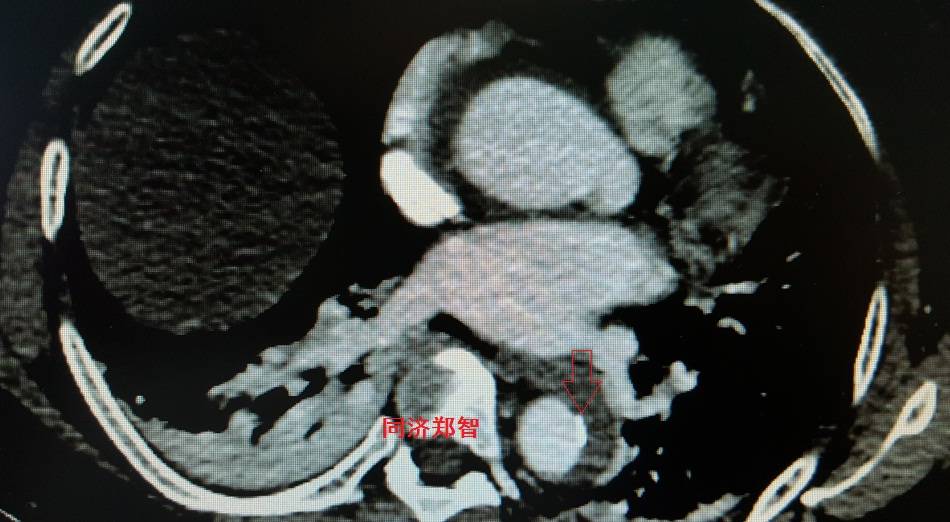

病例四

腹部平扫CT提示腹主动脉增宽,CTA证实为腹主动脉局限性夹层(红箭头所示)